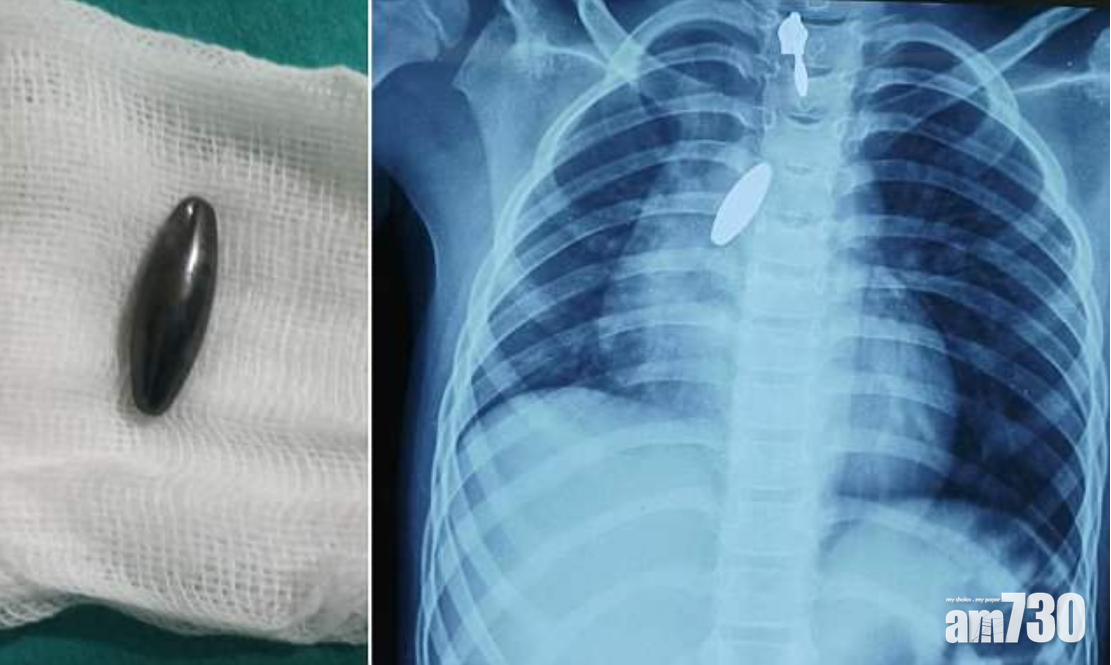

肺卡磁鐵 強力攝石吸出

以毒攻毒,以磁吸磁。印度班加羅爾一名9歲女童玩耍時意外吸入一粒磁鐵,送院救治後,醫生試圖用支氣管鏡檢查儀,夾出附在肺部的1吋長異物,但太滑無法夾穩。最後毋須動手術即將它吸入氣管、再輕易從口而出──妙法是一塊更強的磁石。